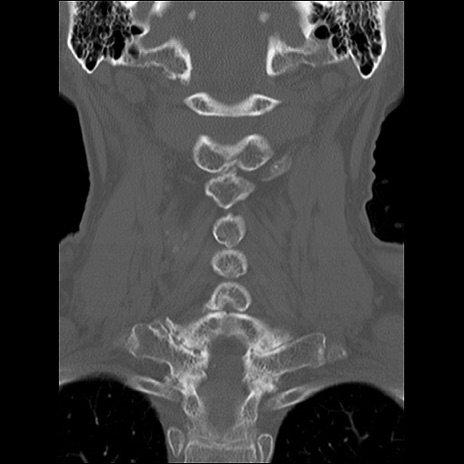

症例48 頚椎CT(冠状断像)

頚椎CT